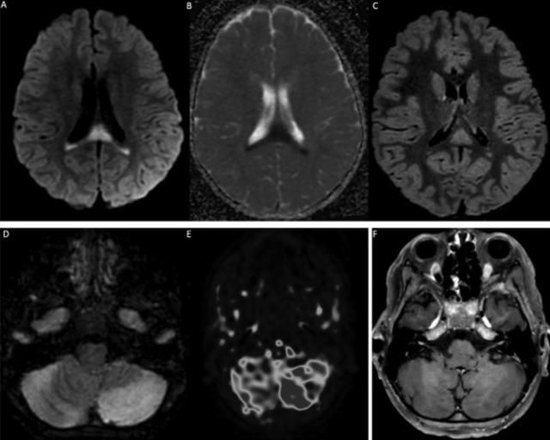

该研究显示,所有患者都有SARS-CoV-2暴露史或核酸检测阳性。在神经系统疾病发作时,8名儿童的新冠病毒核酸检测仍是呈阳性(鼻咽拭子)。58%的患儿(11人)脑脊液异常,74%的儿童(14人)出现MRI异常。

19名患者中有14名MRI异常。4例MRI显示ADEM伴有多灶性脑损伤,1例伴有视神经炎;3例显示胼胝体细胞毒性病变(CLOCC综合征),胼胝体压部扩散受限,T2-FLAIR高信号,2例小脑炎;1例分别显示孤立性视神经炎、孤立性面神经炎和多发性神经炎。19例脊柱MRI中有5例异常:5例显示脊髓炎,其中3例与ADEM相关,1例为孤立性,1例与马尾神经根的对比增强相关。所有脊髓炎病例均显示超过3个椎体受累。